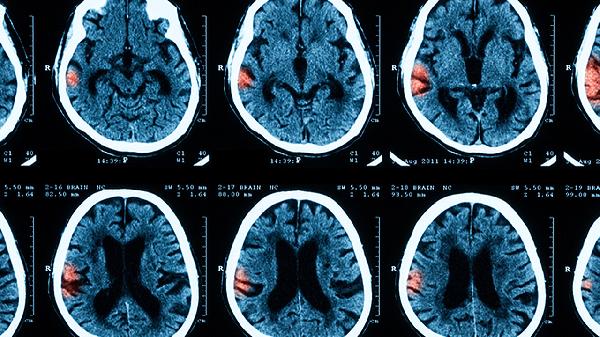

影像学检查如头部CT或MRI可以评估脑膜和脑实质的病变情况,排除其他颅内疾病。CT检查可以显示脑水肿、脑室扩大、脑积水等并发症。MRI对软组织的分辨率更高,能够更清晰地显示脑膜增强、脑实质病变和血管异常。影像学检查在结核性脑膜炎和真菌性脑膜炎的诊断中尤为重要,可以显示基底池增强、脑梗死、肉芽肿等特征性改变。